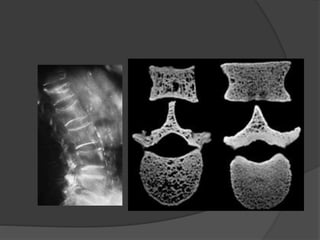

 Classic radiographic findings

include:

widening of the distal epyphysis, fraying

and widening of the metaphysis, and

angular deformities of the arm and leg

bones.

Roentgen-graphic changes:

Wrist is the best site for watching the changes

Widening of the epiphyseal cartilage

Blurring of the cup-shape metaphyses of long bone